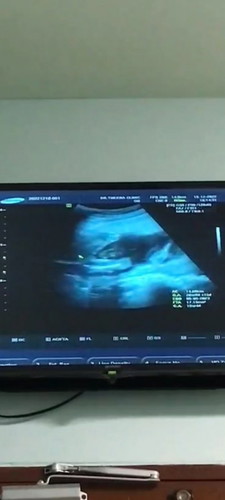

เพศอะไรคะ มีใครดูออกบ้าง

แม่ๆช่วยดูหน่อยค่ะว่าเพศอะไร

เหมือนจะมีสายรกบังนะคะ ยังดูไม่เห็นค่ะ แต่เดาว่าผู้หญิงเพราะไม่เห็นถุงไข่ยื่นออกมา